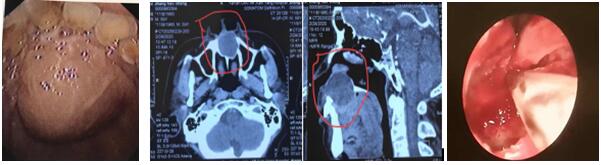

2020年3月3日,經(jīng)耳鼻咽喉科張立剛、尚規(guī)化醫(yī)護(hù)團(tuán)隊(duì)精心準(zhǔn)備,在手術(shù)室醫(yī)護(hù)人員的齊力配合下,耳鼻咽喉科成功完成一例經(jīng)鼻內(nèi)鏡鼻底上頜骨囊腫摘除術(shù)。此類手術(shù)的開(kāi)展,標(biāo)志著我科鼻內(nèi)鏡微創(chuàng)手術(shù)水平再上新臺(tái)階。

患者,男,59歲,因“發(fā)現(xiàn)口腔內(nèi)腫物3月”入院,腫物累及鼻底,并導(dǎo)致鼻底嚴(yán)重隆起,經(jīng)上頜骨CT三維重建檢查,腫物大,且口內(nèi)粘膜因腫物壓迫已很菲薄,還合并腎病綜合癥,口服激素一年余。住院后張立剛主任組織術(shù)前討論,認(rèn)為患者如行傳統(tǒng)經(jīng)唇齦切口手術(shù)方式,極易導(dǎo)致傷口感染或不愈合,引起囗腔鼻腔漏,給患者帶來(lái)災(zāi)難性后果。經(jīng)查閱文獻(xiàn),結(jié)合自身堅(jiān)實(shí)的鼻內(nèi)鏡技術(shù)基礎(chǔ),決定行經(jīng)鼻內(nèi)鏡鼻底上頜骨囊腫摘除術(shù)。手術(shù)取鼻底小切口入路,切開(kāi)黏膜后即見(jiàn)大量粘液溢出,清理后見(jiàn)口腔面黏膜菲薄,透光,與術(shù)前評(píng)估一致,遂將囊腫切除,等離子徹底止血,為防止壓迫導(dǎo)致口腔鼻腔漏形成,摒棄傳統(tǒng)的碘仿紗條壓迫兩周的觀念,術(shù)腔僅填塞可吸收明膠海棉,避免因填塞導(dǎo)致術(shù)后劇烈頭痛等不適。術(shù)后檢查見(jiàn)鼻腔結(jié)構(gòu)完整,口內(nèi)包塊明顯縮小,鼻面部無(wú)任何不適。

上頜骨囊腫在臨床上并不罕見(jiàn),其發(fā)病隱弊,多無(wú)癥狀,當(dāng)發(fā)現(xiàn)上頜骨囊腫時(shí),其上頜骨破壞程度已相當(dāng)嚴(yán)重。傳統(tǒng)手術(shù)方式創(chuàng)傷大,上頜骨骨質(zhì)暴露多,術(shù)后出現(xiàn)頭痛、流淚、面部腫脹及麻木,易增加感染機(jī)會(huì)。